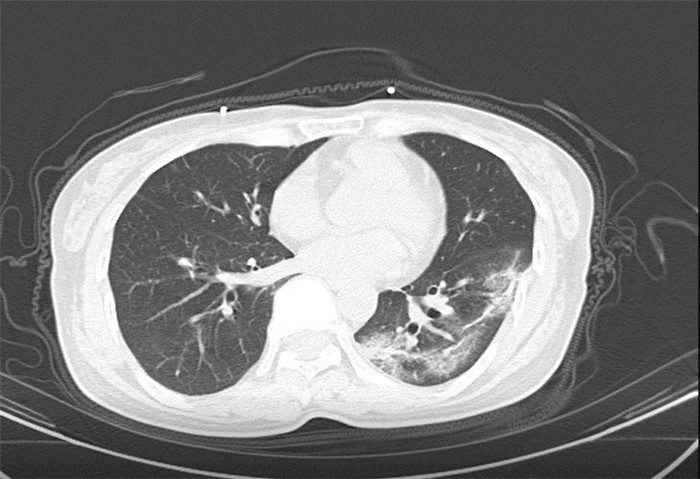

武漢大學(xué)中南醫(yī)院影像科副主任張笑春教授發(fā)現(xiàn),目前武漢市家庭聚集性發(fā)病較多,而且大多起病隱匿,一次甚至多次核酸陰性,無任何臨床癥狀,CT檢查卻已顯示為病毒性肺炎特征。

為了盡快篩查新型冠狀病毒肺炎患者,醫(yī)院會(huì)選擇影像診斷作為早期發(fā)現(xiàn)新型冠狀病毒感染的肺炎的重要一環(huán)。

CT為當(dāng)前首選篩查與診斷的主要影像學(xué)手段,胸部CT的病毒性肺炎檢出率高。

方舟CT(CT Ark)可以滿足全面的臨床功能,配置16層、32層、64層、128層CT,實(shí)現(xiàn)了低劑量掃描要求,配合NDI微劑量迭代技術(shù),智能毫安調(diào)控技術(shù),使各種場(chǎng)合下、各部位低劑量掃描得以實(shí)現(xiàn);超高分辨率CT病灶靶掃描,使病灶的密度顯示更加精確,能夠顯示病灶內(nèi)輕度的密度變化,有利于小病灶的密度定量分析和及時(shí)診斷。